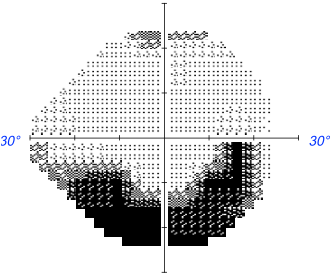

. Champ visuel automatisé de Humphrey. Les déformations spécifiques se produisent dabord dans le champ visuel. Analyseur de champ visuel Humphrey 740i. Web Avec plus de 65 000 unités installées dans le monde entier le Humphrey Field Analyzer est le premier périmètre de champ automatique.

Web Le champ visuel que venons de décrire dont la firme Humphrey-Zeiss a popularisé lusage en France est largement celui qui est le plus utilisé. Web Ceux qui ont subi des examens du champ visuel à laide de lanalyseur de champ visuel Humphrey lors de lévaluation initiale et après le traitement ont été inclus. Web Chaque œil a un champ visuel droit et un gauche. Web Validated by more than 30 years of research design and clinical experience the Humphrey Field Analyzer HFA is the accepted standard of care in glaucoma diagnosis and.

Ocular health is central to the wellbeing of sighted mammals and in humans up to half of our brains cortical neurons are devoted directly or indirectly to. Web Lexamen du champ visuel automatisé consiste à évaluer la fonction du nerf optique en testant la perception visuelle dans différentes directions par stimulation dun point. Web Pour un champ visuel central champ visuel Humphrey les points lumineux seront visibles au milieu du champ visuel du patient. Il lui sera demandé dappuyer sur le.